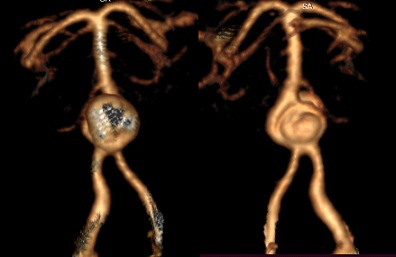

CT revealed a large saccular aneurysm of 13 x 16 mm, with a wide neck (05 mm), implanted on an asymmetric fenestration of the vertebrobasilar junction, without any sign of complication (Figures 1-3).

Figure 3: 3D VRT (Volume Rendering Technique) reconstructions: anterior (A) and posterior (B) views showing the aneurysm developed on the fenestration of the vertebrobasilar junction.